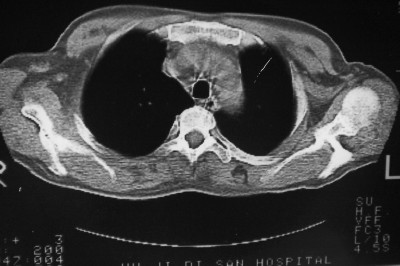

以下是引用天南地北在2007-4-10 1:49:00的发言:[br]考虑右下叶周围型肺癌伴肋骨转移。

以下是引用林建春在2007-4-10 7:35:00的发言:[br]周围型肺癌侵犯肋骨

以下是引用liuyue在2007-4-10 7:56:00的发言:[br]周围型肺癌侵犯肋骨,左肺转移。

以下是引用zhangzhongshou在2007-4-10 10:24:00的发言:[br]右肺下叶背段厚壁空洞,伴胸膜改变、肋骨破坏,其内可见死骨、周围骨质硬化,左肺可见小结节影,[br]单纯影像学更支持结核。建议进一步检查。